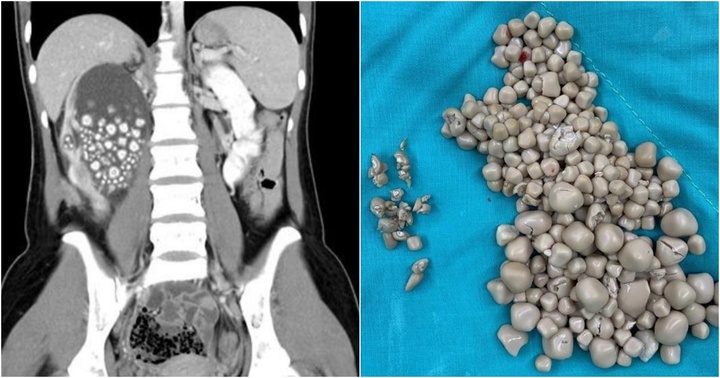

Khi sỏi thận ở mức độ nhẹ, tùy vào loại sỏi thận bạn mắc phải mà một số thay đổi trong chế độ ăn uống có thể giúp cơ thể tự đào thải sỏi ra ngoài. Trong các trường hợp sỏi nặng hơn cần có sự can thiệp của y khoa, bao gồm dùng thuốc để làm tan sỏi hoặc phẫu thuật lấy sỏi. Do đó, khi bị sỏi thận, hãy đi khám chuyên khoa để biết bạn đã mắc loại sỏi thận nào, từ đó các bác sĩ đưa ra những khuyến nghị về chế độ ăn uống để cải thiện bệnh hiệu quả.